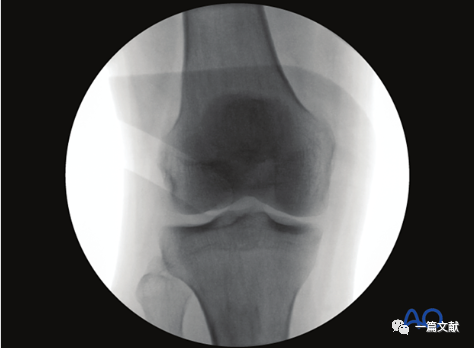

一,标准正位片

1)体位与C臂机位置:取患者仰卧位,患肢完全伸直、中立位;C臂机垂直于患肢放置。如下图:

2)标准正位的评估:1、髌骨下极位于股骨双髁之间 2、腓骨头的1/4-1/3被胫骨外侧平台遮盖。如下图:

3)解剖标志的识别:如下图:1、外侧胫骨平台关节面 2、髌骨 3、腓骨头4、内侧胫骨平台5、外侧髁间脊6、内侧髁间脊。

4)标准正位的意义:1、评估关节内骨折块复位情况(关节面台阶)2、检视关节内的游离骨块或突入关节的内植物3、内翻或外翻应力下关节间隙变化情况(侧副韧带损伤指征)4、髁间脊撕脱骨折的评估(叉韧带损伤情况)5、评估胫骨关节线和胫骨轴线之间的角度(85-90°)。